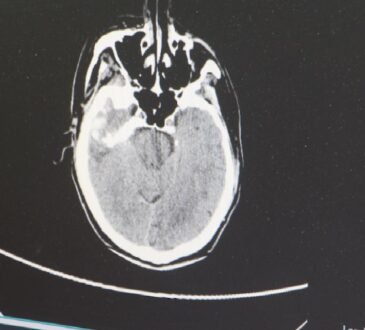

Hafta sonu kaçamağı olarak görülen yağlı bir yemek, sandığınız kadar masum olmayabilir. Güney Galler Üniversitesi’nden bilim insanlarının yürüttüğü yeni bir araştırmaya göre, sadece bir adet yüksek doymuş yağ içeren öğün bile beyne giden kan akışını bozabiliyor. Bu bozulma, uzun vadede felç ve bunama gibi ciddi hastalıkların riskini artırabilir.